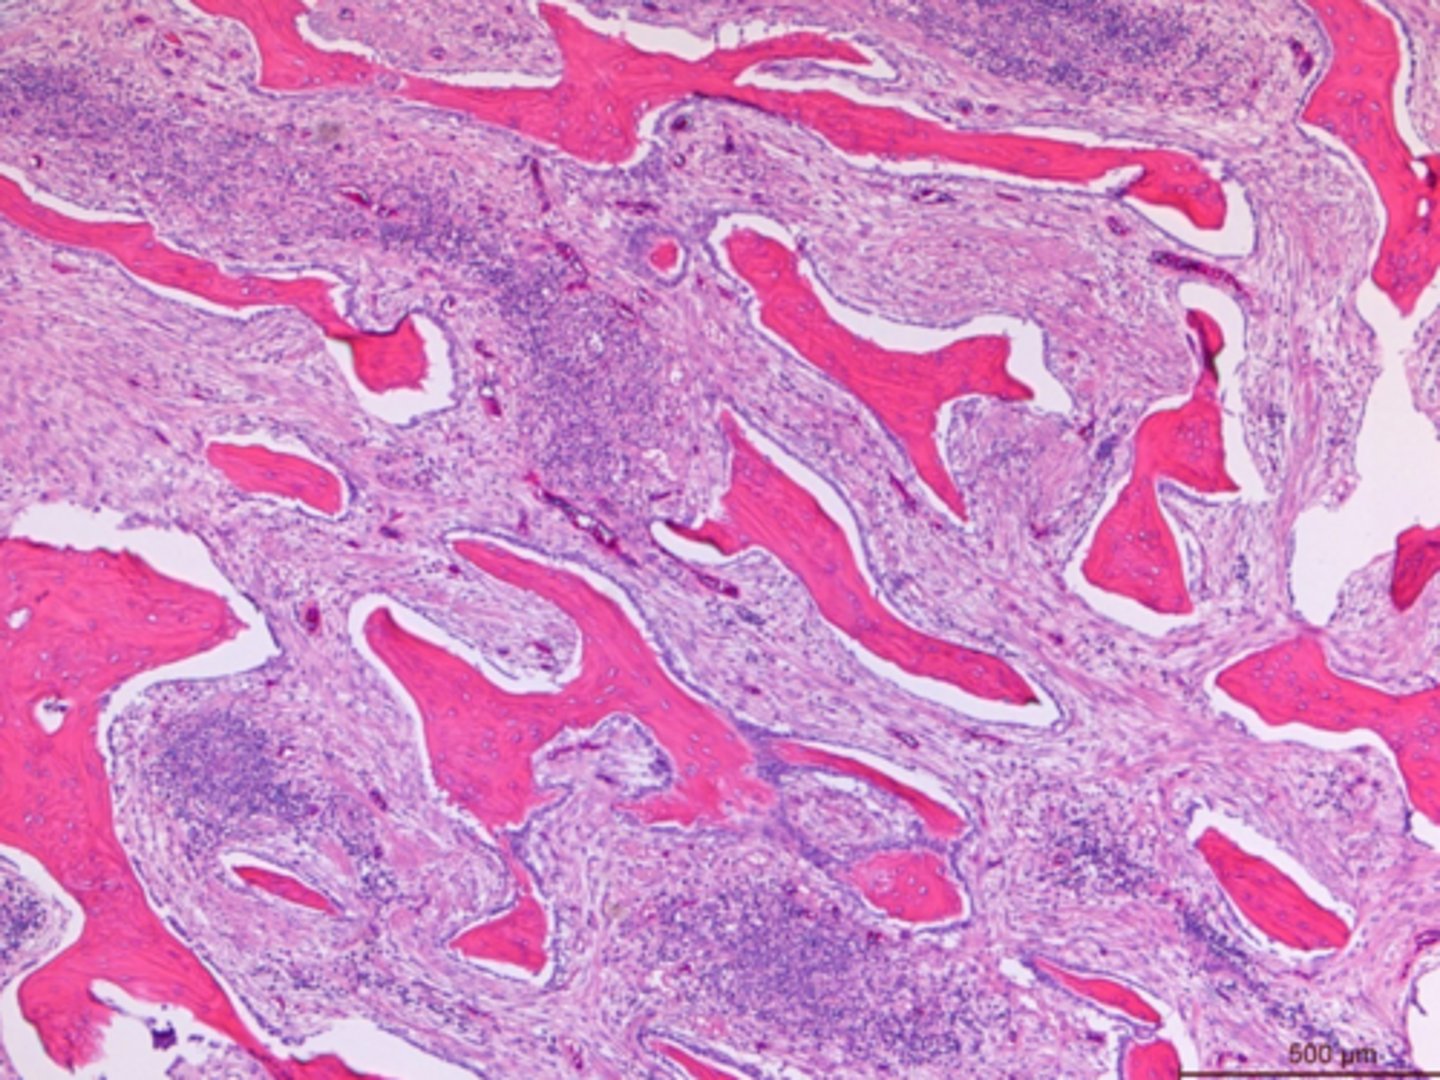

Identify the pathology:

Fiberous osteodystrophy